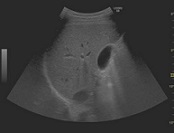

団塊の世代が75歳以上となる、いわゆる「2025年問題」を前に、医療サービス提供のあり方に変革が求められてきている。その中で、超音波検査は精度の向上と診断の効率化に貢献することから、その活用に期待が高まっている。超音波検査は体への負担が少なく、リアルタイムの画像化によるさまざまな領域の検査が可能であるが、一般的にCTやMRIと比べ視野深度が限られ、体格によっては深部まで超音波が届きづらいことや浅い部分(表在)の抽出が困難であることが課題とされてきた。また、動くことが難しい高齢の患者にとっては診断装置のある検査室まで行くことが難しい場合もあり、軽くて検査室外への持ち運びがしやすく、質の高い検査を可能とする超音波診断装置の開発が求められてきた。 この度発売される「LOGIQ S8 with XDclear」と「LOGIQ E9 with XDclear2.0」は、日野本社で開発された高感度プローブ「XDclearプローブ」の搭載により、体の浅部から深部にいたるまで超音波を届けることが可能になった。腹部一般用の「C1-6-Dプローブ」は、深部の観察範囲を広げることで、体格による画像抽出困難を軽減し、形状が小さいマイクロコンベックスタイプの浅部用「C3-10-Dプローブ」は、血管、小児、腹部など全身のさまざまな部位にあてやすく、表在部の画像の多重エコーなどを解決。

腹部一般用の「C1-6-Dプローブ」と浅部用の「C3-10-Dプローブ」の搭載により、浅部や深部の画質向上を実現。一台で多様な質の高い検査を可能とする。

同社では、GEヘルスケアの中核開発・製造拠点として、これまで30年以上にわたり世界の医療現場に日本発の先進プローブを届けてきた開発・製造チームの密な連携のもと、プローブの素材を見直し、従来のセラミックに替えて、電気信号と音の変換効率に優れたシングルクリスタル(高密度単結晶)を採用し、これまで使用されていなかった音響エネルギーを有効活用するアコースティックアンプリファイヤー技術、ならびにレンズ表面での温度上昇を抑えてプローブが最大限の性能を発揮できるようにするクールスタック技術を搭載することで、この課題を克服。画質と診断深度の両立を可能にするXDclearプローブの開発で、皮膚に近い表在部から体内深部まで広範囲にわたって均一な高精細画像の描出を可能とした。